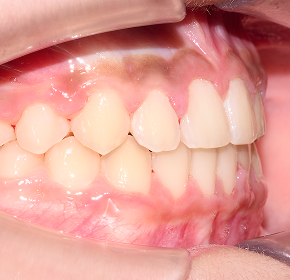

BEFORE / AFTER

전후 변화로 보는 치료사례

본 사진은 진심을담은치과교정과 치과의원에서

치료한 환자의 동일 인물 전·후 사진입니다.

개인의 구강 상태 및 관리 방법에 따라 통증 및 잇몸 염증,

턱관절 불편감 등의 부작용이 발생할 수 있습니다.

치료 전 치료 후

덧니, 삐뚤한 치열